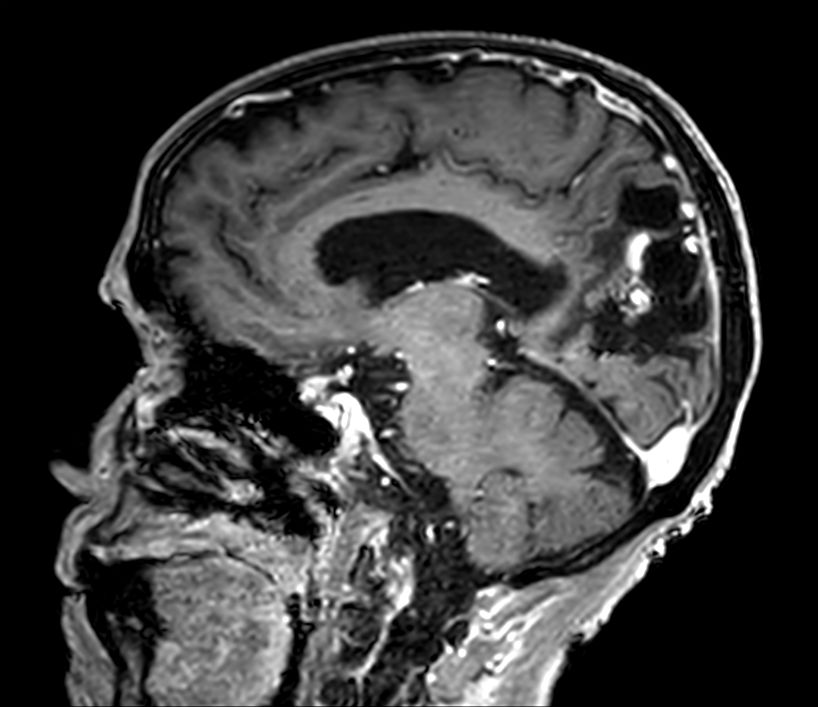

Sagittal 3D T1w FFE +gado

3D T1w FFE (axial reformat) +gado

3D T1w FFE (coronal reformat) +gado